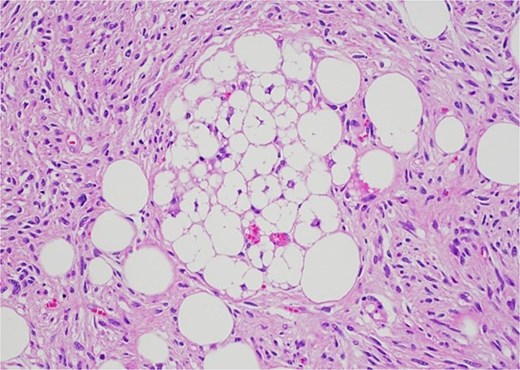

Histology revealed a multilobulated spindle cell lesion, with low- and high-grade areas, with an abrupt transition between these areas. There was an adjacent focus of adipose tissue with rare cytologic atypia suggestive of possible WDL, which indicated that the tumor mass may represent DDL. However, there was a single focus of lipoblasts identified, bringing up the differential of pleomorphic liposarcoma. Therefore, in situ hybridisation was performed and showed MDM2 amplification, which confirmed the diagnosis of DDL, with likely homologous lipoblastic morphology. The tumour was excised with clear margins (Figs 3–8).

Low-grade component with spindle cells with tapered nuclei and indistinct cytoplasm that merges into a delicate collagenous stroma.